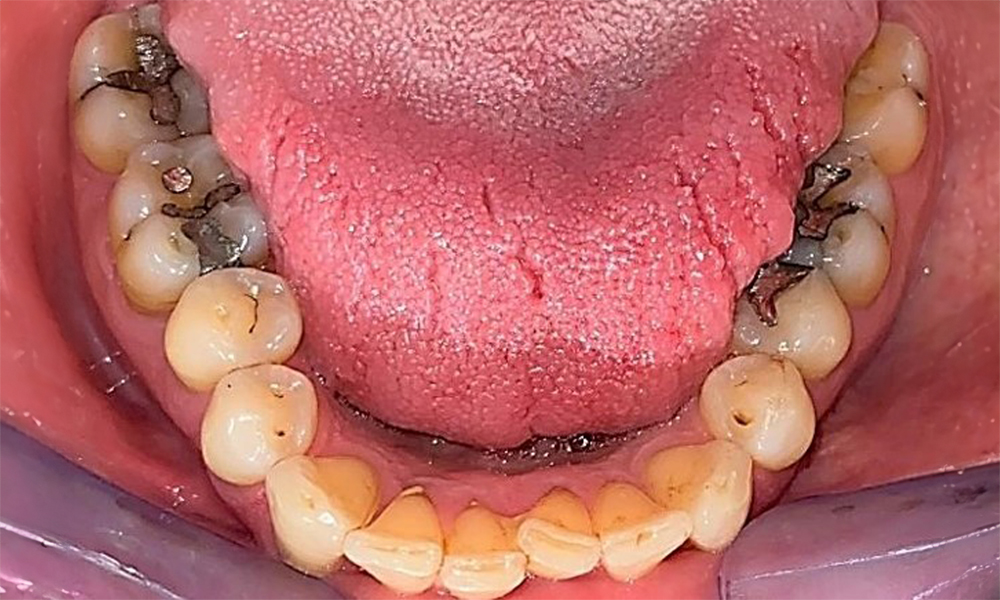

Okklusalansicht Unterkiefer zur Darstellung der vorhandenen Restaurationen. © Dr. R. Krapf

Abb. 6 Okklusalansicht Unterkiefer zur Darstellung der vorhandenen Restaurationen. © Dr. R. Krapf

Der Patient hat ein vollbezahntes Gebiss mit 28 Zähnen, an welchen sich im Molaren- und Prämolarenbereich Amalgamfüllungen und Compositefüllungen befinden. An Zahn 14 zeigt sich ein sichtbarer klinischer Randspalt. Zahn 27 hat ein suffizientes Goldinlay. Zudem zeigen sich generalisierte Attritionen und Abrasionen. (Abb. 2, Abb. 3, Abb. 4, Abb. 5, Abb. 6)